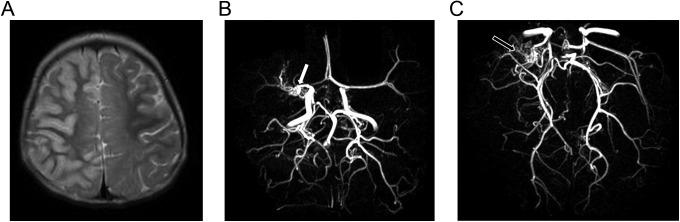

Vascular wall injuries account for up to 80% of childhood strokes, excluding emboli of cardiac origin. Transient cerebral arteriopathy is a recently described entity that is increasingly recognized as an important cause. The cerebral arterial wall is thought to be affected by an inflammatory process related to certain infections. The authors report a 2.5-year-old girl with sudden left hemiplegia and aphasia. The neuroimaging showed occlusion of the right middle cerebral artery and ischemic damages. Laboratory revealed positive cytomegalovirus immunoglobulin M and G in cerebrospinal fluid and in early and late sera. Treatment with ganciclovir, anticytomegalovirus immunoglobulin, and prednisolone, followed by oral aspirin, resulted in clinical improvement. The follow-up neuroimaging showed stabilization of the arterial lesions without residual stenosis. To our knowledge, this is the first report of a cytomegalovirus-associated transient cerebral arteriopathy in an immunocompetent child. Our report demonstrates the propensity for cytomegalovirus to be involved in pediatric cerebral vascular disease.

血管壁损伤占儿童中风的比例高达80%,不包括心源性栓子。短暂性脑动脉病是一种最近描述的疾病,越来越被认为是一个重要病因。脑动脉壁被认为受到与某些感染相关的炎症过程影响。作者报告了一名2.5岁突发左侧偏瘫和失语的女孩。神经影像学检查显示右侧大脑中动脉闭塞及缺血性损伤。实验室检查显示脑脊液以及早期和晚期血清中巨细胞病毒免疫球蛋白M和G呈阳性。使用更昔洛韦、抗巨细胞病毒免疫球蛋白和泼尼松龙治疗,随后口服阿司匹林,临床症状有所改善。随访神经影像学检查显示动脉病变稳定,无残余狭窄。据我们所知,这是首例免疫功能正常儿童巨细胞病毒相关性短暂性脑动脉病的报告。我们的报告证明了巨细胞病毒参与小儿脑血管疾病的倾向。